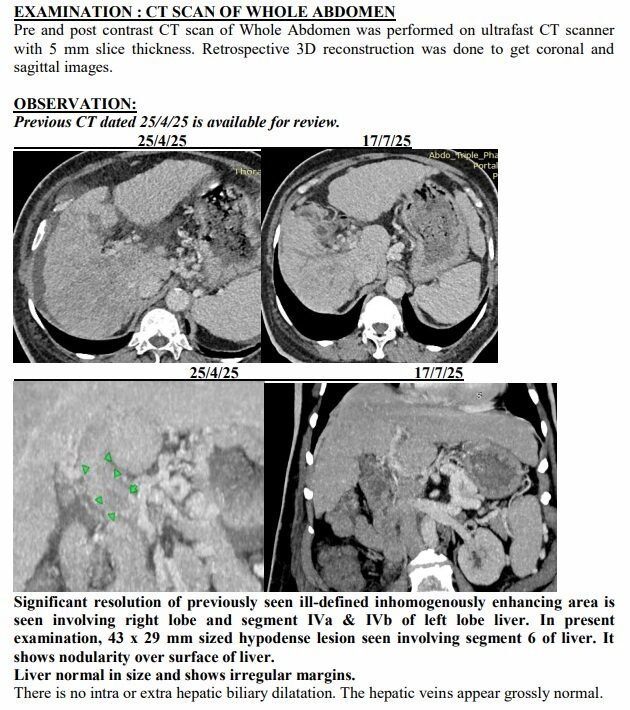

Yet just three months later, on another afternoon in July, the same family stared at a different scan. The tumours had shrunk to one patch. Blood was flowing again. The swelling was gone. Even the alarming tumour marker that had shot up to 1,000 ng/mL had fallen to 10, back in the safe zone. For a man who had been fading fast, it was a turnaround no one in the room dared to predict.

Ravjibhai’s case became proof of concept. Prescribed a personalised herbal regimen meant to reduce tumour load, restore liver function and boost immunity, he began showing slight changes in weeks. The fever broke. Jaundice eased. He ate a little more each day and walked a little further. His family noticed he was laughing again, something they hadn’t heard in months.

The July scan sealed what they were already feeling at home. The many shadows in his liver had shrunk into one. His abdomen, once swollen with fluid, was flat again. His numbers, which had scared even seasoned oncologists, were suddenly within range.